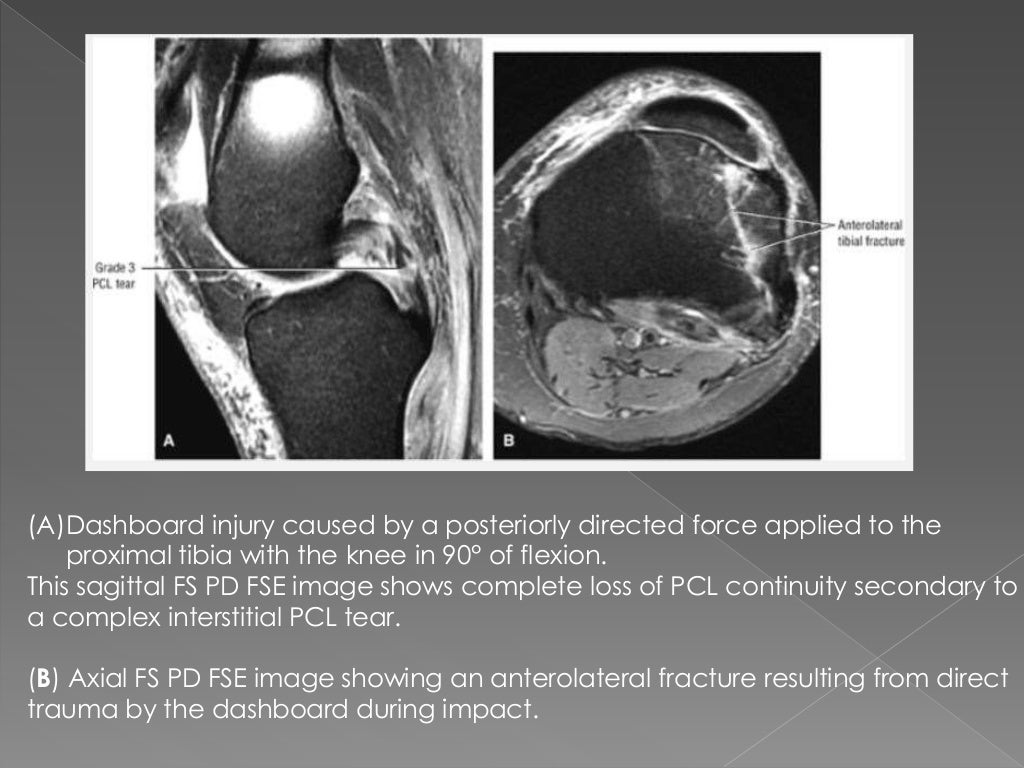

Dashboard Injury Knee Radiology . the pattern of bone bruise in knee injuries (a.k.a. the most common injuries involve the soft tissues, including ligaments, cartilage, and menisci. Bone contusion) can give clues for the mechanism and associated. Valgus stress to flexed and externally. Commonly occurs when force is applied to the anterior aspect of the tibia whilst the knee is flexed such as the. a direct blow to the proximal anterior tibia in a flexed knee with forceful posterior displacement of the tibia usually results in a midsubstance tear, often with disruption of the posterior capsule. Dashboard injuries and falls on a hyperflexed knee are common examples of this mechanism of injury. in dashboard injury, a posteriorly directed force is applied to the anterior aspect of proximal tibial while the knee is in a flexed position. dashboard knee injuries are a fairly common mechanism of trauma in seatbelted passengers involved in road traffic.